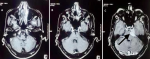

Diagnostic assessment: the patient was admitted under the Department of Neurosurgery. All routine investigations, including chest X-ray and electrocardiography, were conducted and were found to be within normal limits. A previously performed MRI of the brain revealed an extra-axial lesion in the left cerebellopontine (CP) angle with a broad-based dural attachment, intense post-contrast enhancement, and a positive dural tail sign. The lesion caused indentation and distortion of the brainstem, with no evidence of vertebrobasilar abnormality, findings suggestive of a meningioma (Figure 1). Based on the clinical presentation and imaging features, a preliminary diagnosis of a left CP angle tumour was made, and the patient was scheduled for retro-mastoid craniotomy with excision of the left CP angle tumour. Intraoperatively, a well-encapsulated, greyish-white, globular mass approximating 2.4 x 1.9 cm was noted. The tumour was moderately vascular, firm in consistency, and adhered to the trigeminal nerve. The surgery was uneventful, with no trace of active bleeding or cerebrospinal fluid leakage prior to closure. The excised tissue was submitted for histopathological examination. Grossly, the specimen comprised multiple, irregular, greyish-brown fragments measuring approximately 2 x 1 x 0.5 cm (Figure 2). Microscopic evaluation demonstrated alternate hypocellular and hypercellular areas producing a marbling effect (Figure 3(A, B)). Sections also showed a uniform population of spindle-shaped cells with slender, pleomorphic, hyperchromatic nuclei displaying folded contours (Figure 4). Immunohistochemical evaluation was carried out to further substantiate the diagnosis. The cells demonstrated strong positivity for vimentin (Figure 5 A), a markedly raised Ki-67 index of about 90% (Figure 5 B), while being negative for SOX-10 (Figure 5 C) and S-100 (Figure 5 D).

Figure 1: A,B,C) magnetic resonance imaging of the brain, causing post-contrast enhancement with a positive dural trail sign